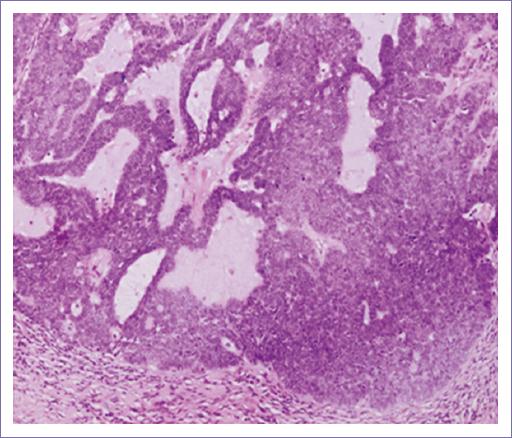

– Descripción microscópica. Los cortes histológicos examinados muestran la piel que presenta la epidermis sin alteraciones (Fig. 1); subyacente se observa tumor maligno de anexos cutáneos con patrón de crecimiento sólido, con proliferación de células de aspecto basaloide con núcleos vesiculosos. Pleomorfismo moderado y un índice mitósico de 4xCSF (40x) (Fig. 2). La neoplasia presenta formación de lúmenes intracitoplásmicos multifocales (Fig. 3). Los bordes del tumor son infiltrativos a nivel de dermis reticular (Fig. 4). No se identifica permeación vascular linfática. El lecho quirúrgico y bordes quirúrgicos no presentan lesión neoplásica.